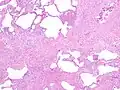

Histology

The histologic hallmarks of UIP, as seen in lung tissue under a microscope by a pathologist, are interstitial fibrosis in a "patchwork pattern", honeycomb change and fibroblast foci (see images below).[6] [7]